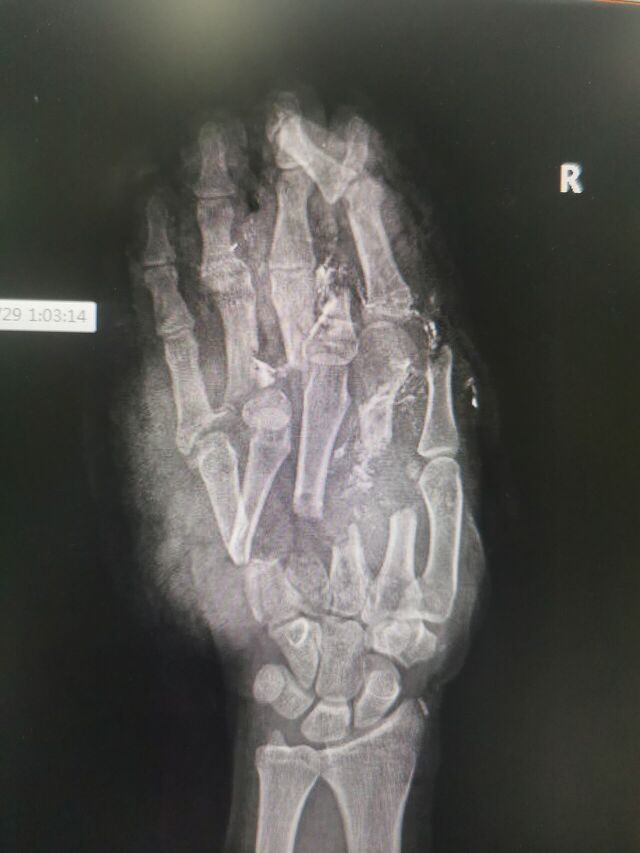

注定又是一个不眠夜!

等待119来破拆

16岁手进绞肉机了